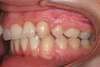

Jeune adulte traitée en technique linguale

A-Début